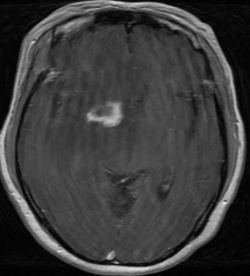

MRI Brain in TE patient